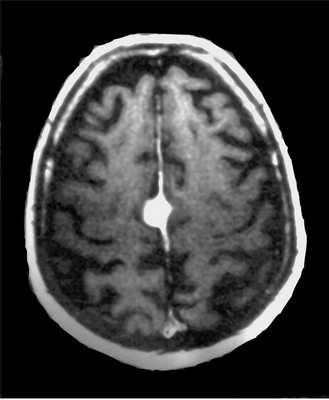

Тот же пациент. Внутрижелудочковая менингиома. Аксиальная Т2-зависимая МРТ, поперечная и сагиттальная Т1-зависимые МРТ с контрастированием.